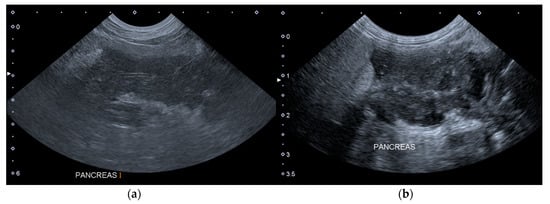

The Figure 1 shows two ultrasound images of the pancreas of a dog included in the Group A, which presented one additional HAS on T1.

Figure 1. Longitudinal ultrasound images of the right lobe of the pancreas of a dog included in the group A. (a) T0: the pancreas is enlarged, hypoechoic, slightly inhomogeneous and with peripancreatic hyperechoic mesenteric fat. (b) T1: the pancreas is more inhomogeneous and with peripancreatic free fluid. T0: abdominal ultrasound examination performed on the first day of hospitalization; T1: abdominal ultrasound examination performed on the third day of hospitalization.

Based on the hypothesis formulated in a veterinary study according to which the findings observable on the AUE may vary based on the time elapsing since the onset of AP, we analyzed four groups [15]. The dogs belonging to group A had an AUE positive for AP on both T0 and T1. In these dogs, the visible ultrasonographic macroscopic damage induced by the AP probably occurred early, allowing an immediate visualization of the ultrasonographic alterations. It cannot be excluded that dogs belonging to this group were presented to the veterinary hospital some days after from the onset of AP, and therefore the time necessary for the microscopic damage to become ultrasonographically evident had already passed. In group A, pancreatic hypoechogenicity and peripancreatic free fluid were evident in the same number of dogs on both T0 and T1, while we observed an increase in other HSAs between T0 and T1.